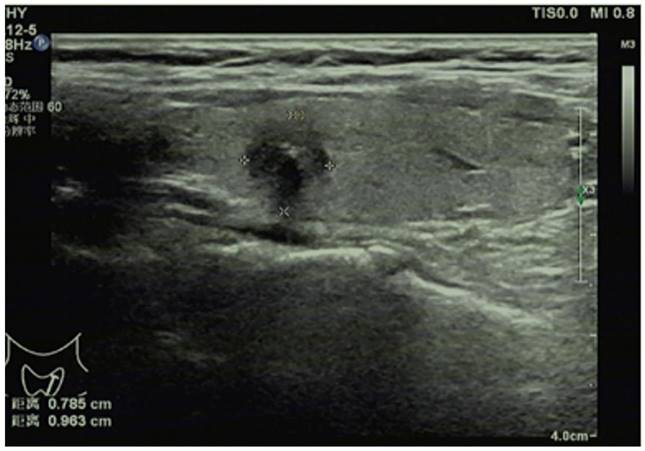

Conventional ultrasonography method

Doppler ultrasound diagnostic instrument (LOGIQ E8, GE, USA) equipped with 4-18 MHz linear array probes was employed for conventional ultrasonography of thyroid glands and cervical lymph nodes (Figure 1). In brief, the bilateral lobes and isthmus of thyroid glands were scanned for the transverse section and then for the sagittal section from top to bottom, and the conventional ultrasonic image data were recorded in detail, including the shape, size, echo and blood flow of thyroid glands. After finding nodules, the following parameters were recorded: the maximum lesion diameter, number of nodules (single or multiple), aspect ratio of lesions (≥1 or <1), location (right lobe, left lobe, or isthmus), echo (hyperechoic or isoechoic, or hypoechoic/extremely hypoechoic), margin (smooth, lobulated or irregular), capsule invasion (yes or no), calcification (yes or no), and blood flow distribution (Grade 0, I, II, or III, assessed by Adler's blood flow grading standard, with Grade 0 for no blood flow signal in lesions, grade I for existence of 1-2 thin short rod-like/dot blood flow signals in lesions, Grade II for presence of 1 relatively long blood vessel or 3-4 thin short rod-like/dot blood flow signals in lesions, and Grade III for existence of 2 relatively long blood vessels or more than 5 thin short rod-like/dot blood flow signals in lesions). Thereafter, all-round scan of cervical lymph nodes was conducted, with a high frequency linear array probe for continuous scan from the submentum to the jaw.

Figure 1

Conventional ultrasonography for papillary thyroid carcinoma.